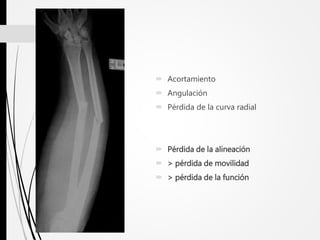

 Acortamiento

 Angulación

 Pérdida de la curva radial

 Pérdida de la alineación

 > pérdida de movilidad

 > pérdida de la función

 Acortamiento  Angulación Pérdida de la curva radial  Pérdida de la alineación  > pérdida de movilidad  > pérdida de la función